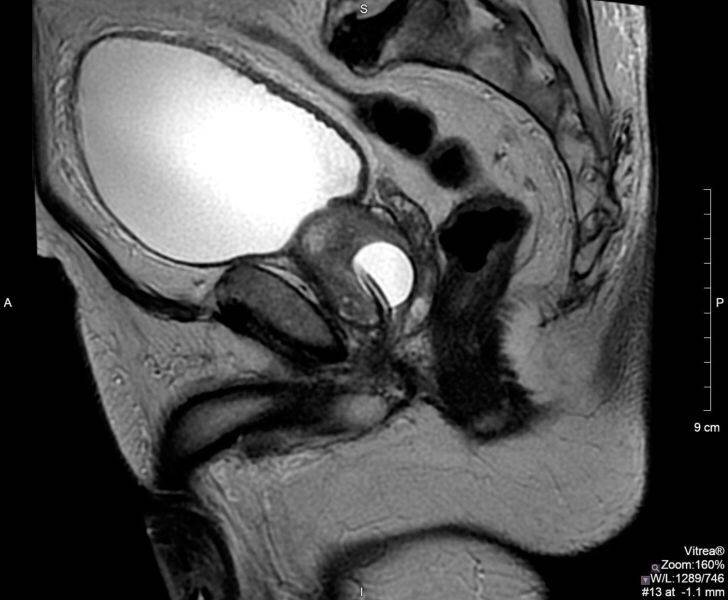

МРТ простаты

Что покажет МРТ простаты

В рамках МРТ предстательной железы врач будет оценивать следующие аспекты:

• Размер и объем предстательной железы;

• Переходная зона расширена или нет вследствие доброкачественной гиперпилазии;

• Имеются ли следы кровоизлияний;

• Капсула железы ровная без асимметричного выбухания или инвазии;

• Имеется или нет распространение за капсулу справа или слева в области ректопростатического угла/нейроваскулярного пучка;

• Семенные пузырьки не изменены;

• Размер мочевого пузыря и наличие утолщений в его стенках;

• Лимфатические узлы не увеличены;

• Есть ли признаки очаговых изменений в костных тканях.

По результатам МРТ простаты диагност напишет детальное заключение, сопроводив его томограммами. Весь этот пакет документов получит пациент (расшифровка снимков в среднем занимает 30- 40 минут), и, в зависимости от итогов сканирования, он будет направлен либо к своему лечащему врачу для постановки окончательного диагноза и начала терапии, либо на дообследование.